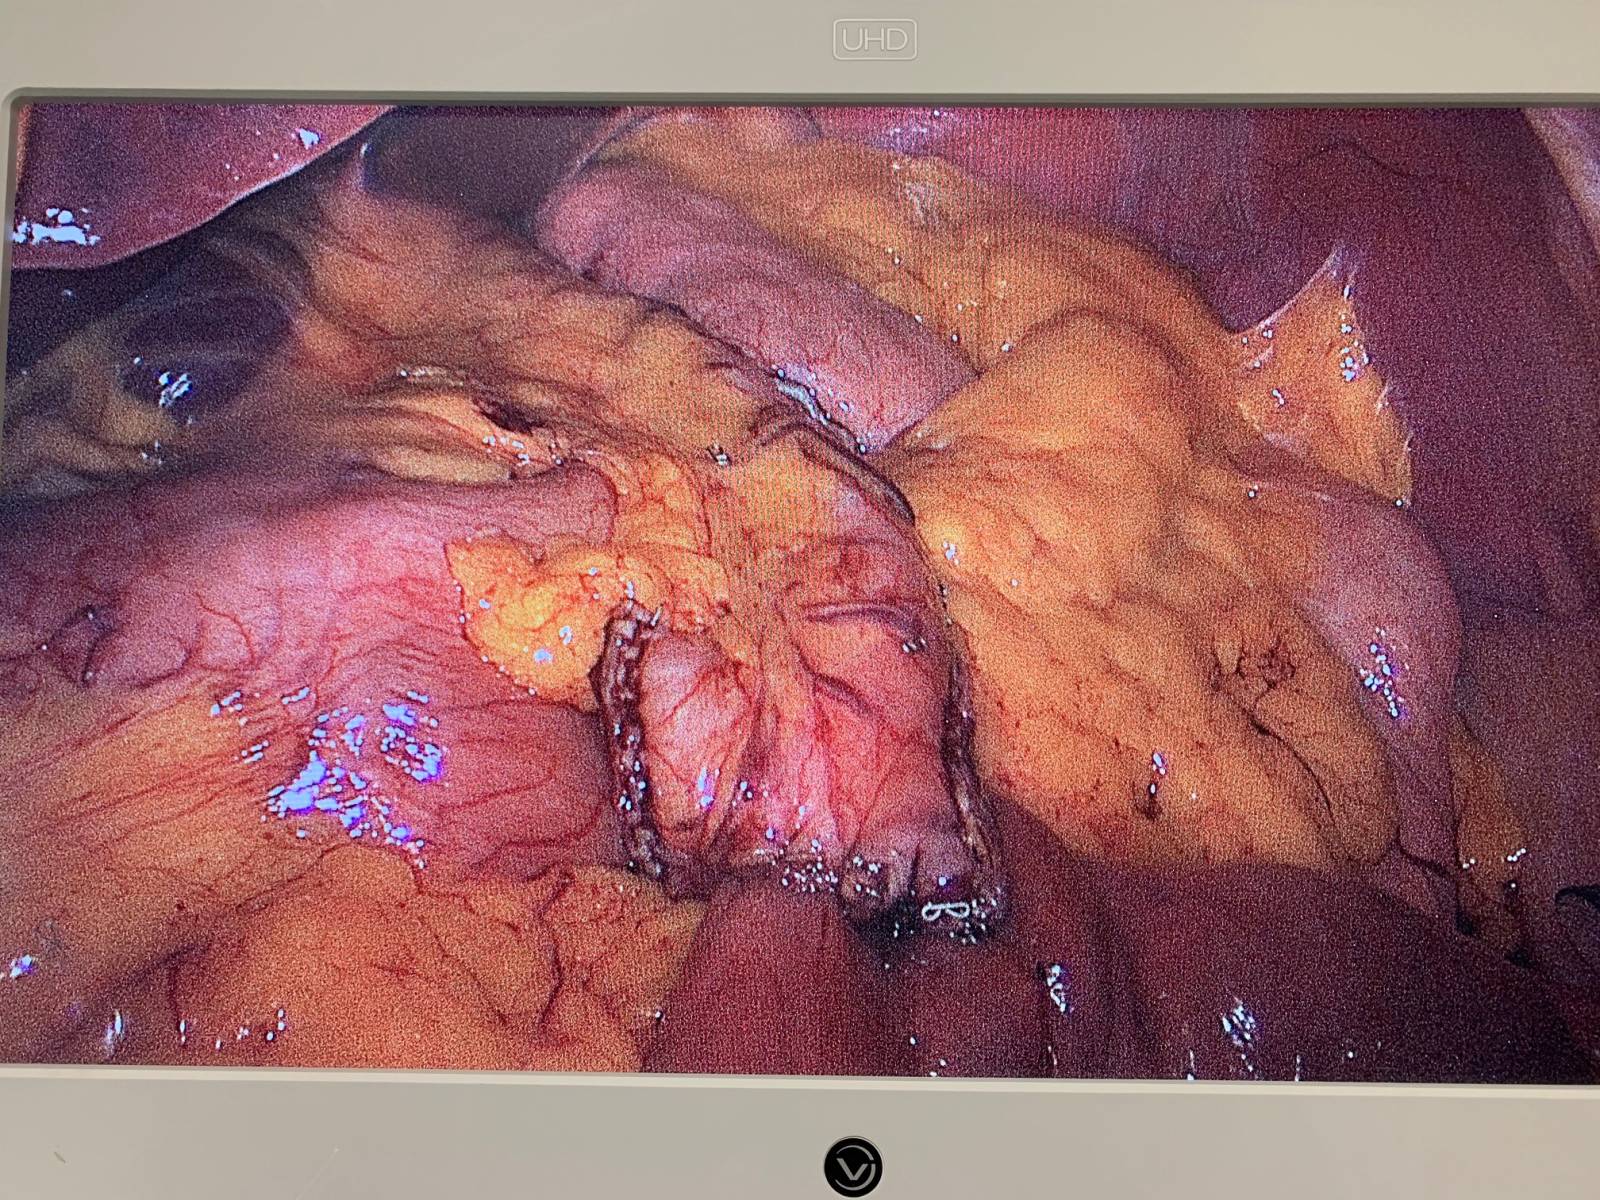

Traitement chirurgical des hernies internes après bypass en Y: une Expertise du groupe MUST à Paris

La hernie interne (HI) fait partie des complications chroniques les plus fréquentes après bypass gastrique en Y (BPGY). L’incidence de cette complication dép...